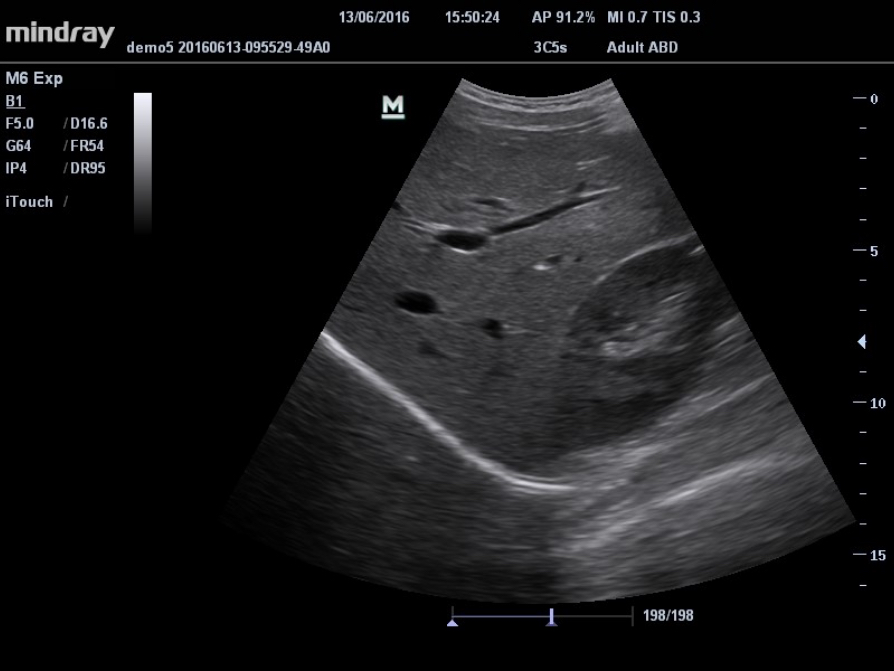

Toma de im√°genes de contraste UWN (Ultra-Wideband Non-linear, Ultra-ancho de banda no lineal)

La toma de imágenes de contraste UWN permite al M6 detectar y utilizar la segunda armónica y las se?ales fundamentales no lineales, lo que permite generar imágenes con mejoras significativas.

- Se?al menor m√°s sensible, dosis de agente reducida

- Duración de agente más larga con requisito MI más bajo